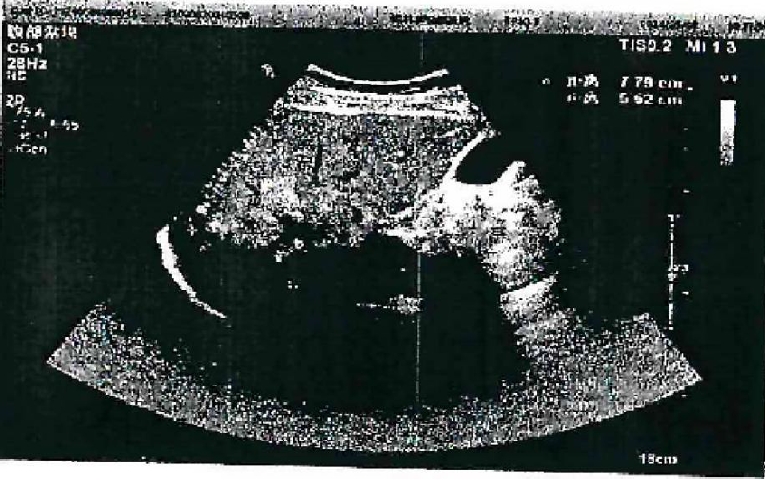

Ultrasound showed a heterogeneous hyperechoic mass (7.8×5.5 cm) with unclear borders in liver segments S4, S7, and S8 (Fig. 1). Computed tomography suggested a large, poorly defined mass with mixed density and patchy calcifications (maximum cross-sectional area 15.11×11.29 cm) in the liver. No enhancement was observed in dynamic contrast imaging. A low-density lesion in the left adrenal gland showed no enhancement (Fig. 2A). The right portal vein was narrowed. The right and middle hepatic veins were partially obscured in the portal venous phase (Fig. 2B). The presence of a large, infiltrative mass with heterogeneous density and irregular calcifications is a recognized, though not universal, imaging presentation of advanced alveolar echinococcosis, which can mimic malignancy.

Fig. 1.

Abdominal color doppler ultrasound showed a heterogeneous.

Fig. 1. Abdominal color doppler ultrasound showed a heterogeneous.